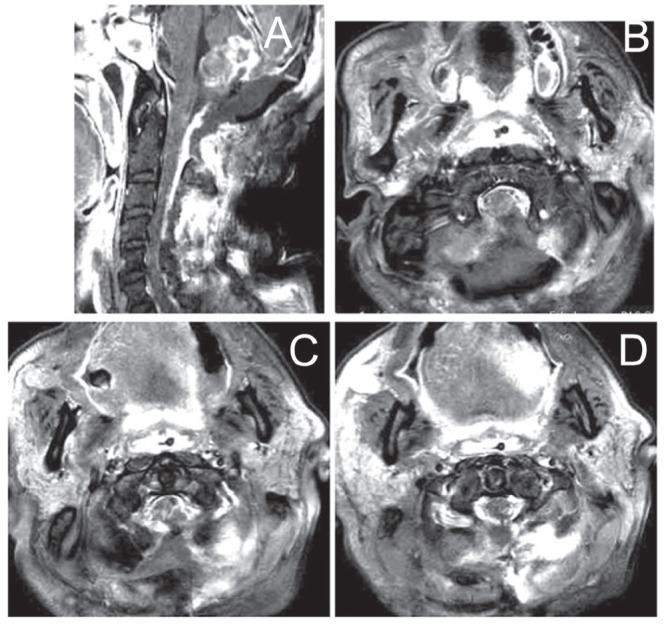

This report describes a rare case of a patient with growth hormone (GH)-secreting pituitary adenoma with malignant transformation resulting in multiple metastases to the dura mater of the cerebral convexity and high cervical spine. The patient was a 60-year-old man with a previous history of pituitary adenoma with suprasellar extension who had undergone transsphenoidal surgery, craniotomy for a convexity tumor, and suboccipital craniotomy for a cerebellar tumor. Thirteen years after the initial surgery, suboccipital craniotomy for a cervicomedullary junction tumor and cervicospinal surgery for a metastatic tumor was performed. Histologic findings of resected specimens demonstrated that the primary pituitary tumor was typical adenoma (similar to specimens from the initial surgery) but that the cerebellar and the dural tumor from the high cervical spine had a high incidence of mitotic figures, and cellular anaplasia with nuclear polymorphism and necrosis. In addition, the serum levels of GH were noted to have decreased with recurrence of the tumor. It was concluded that patients with pituitary adenoma, even when benign, must be carefully followed for signs of malignant transformation, and spinal or distant metastases.

本报告描述了一例罕见病例,患者为分泌生长激素(GH)的垂体腺瘤发生恶性转化,导致大脑凸面硬脑膜和高颈段脊柱多发转移。患者为一名60岁男性,既往有垂体腺瘤伴鞍上延伸病史,曾接受经蝶窦手术、凸面肿瘤开颅手术以及小脑肿瘤枕下开颅手术。初次手术后13年,因颈髓交界处肿瘤行枕下开颅手术,并因转移性肿瘤行颈脊髓手术。切除标本的组织学检查结果显示,原发性垂体肿瘤为典型腺瘤(与初次手术标本相似),但小脑和高颈段脊柱的硬脑膜肿瘤有较高的有丝分裂象发生率,以及伴有核多形性和坏死的细胞间变。此外,随着肿瘤复发,血清GH水平下降。得出的结论是,垂体腺瘤患者即使是良性的,也必须密切随访,观察有无恶性转化迹象以及脊柱或远处转移。